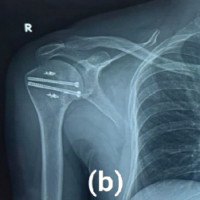

Recognizing the bilateral AFFs and the imminent risk of a right-sided fracture, prophylactic intramedullary nailing was performed on the right femur (Fig. 3), based on the current clinical evidence. This approach also facilitated positioning for subsequent fracture reduction and reconstruction nailing of the left femur (Fig. 4), conducted 2 days later. The postoperative course was uneventful. Bisphosphonate therapy was discontinued, and the patient was started on teriparatide injections, calcium, and vitamin D supplementation. After satisfactory post-operative X-rays (Fig. 5), full weight-bearing mobilization with walker support was initiated.

Six weeks into rehabilitation, during one of the mobilization sessions, the patient reported pain at the site of prophylactic nailing in the right femur. Radiographs revealed a minimally displaced fracture in the proximal third of the right femur (Fig. 6). Conservative management was pursued due to the absence of significant displacement or angulation, which was probably due to the prophylactic nail in situ. Mobilization was restricted to bedside exercises for 6 weeks, followed by a gradual return to full weight-bearing activity. There was no complaint of worsening of pain or any other symptoms with this conservative approach. With regular clinical and radiological follow-ups, the patient demonstrated progressive healing, transitioning to single crutch-assisted ambulation by 6 months. One-year post-surgery, complete bilateral fracture consolidation was observed (Fig. 7), and the patient achieved unaided, pain-free mobility. She is still under follow-up and is doing well, with no further symptoms so far.